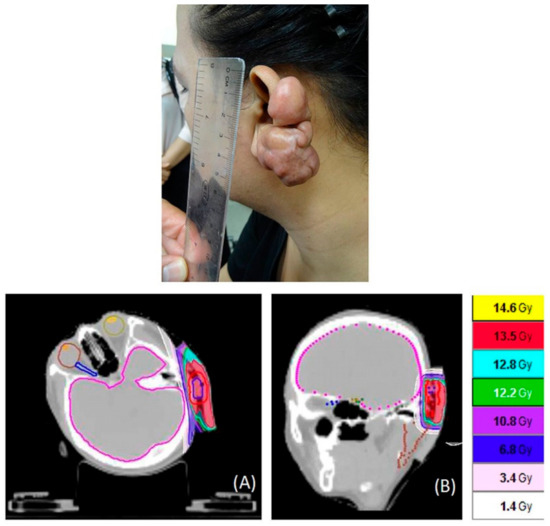

2.2. CT Simulation for HT

2.3. Target Contouring, Treatment Planning, and Treatment by HT

2.4. Plan Evaluation for HT